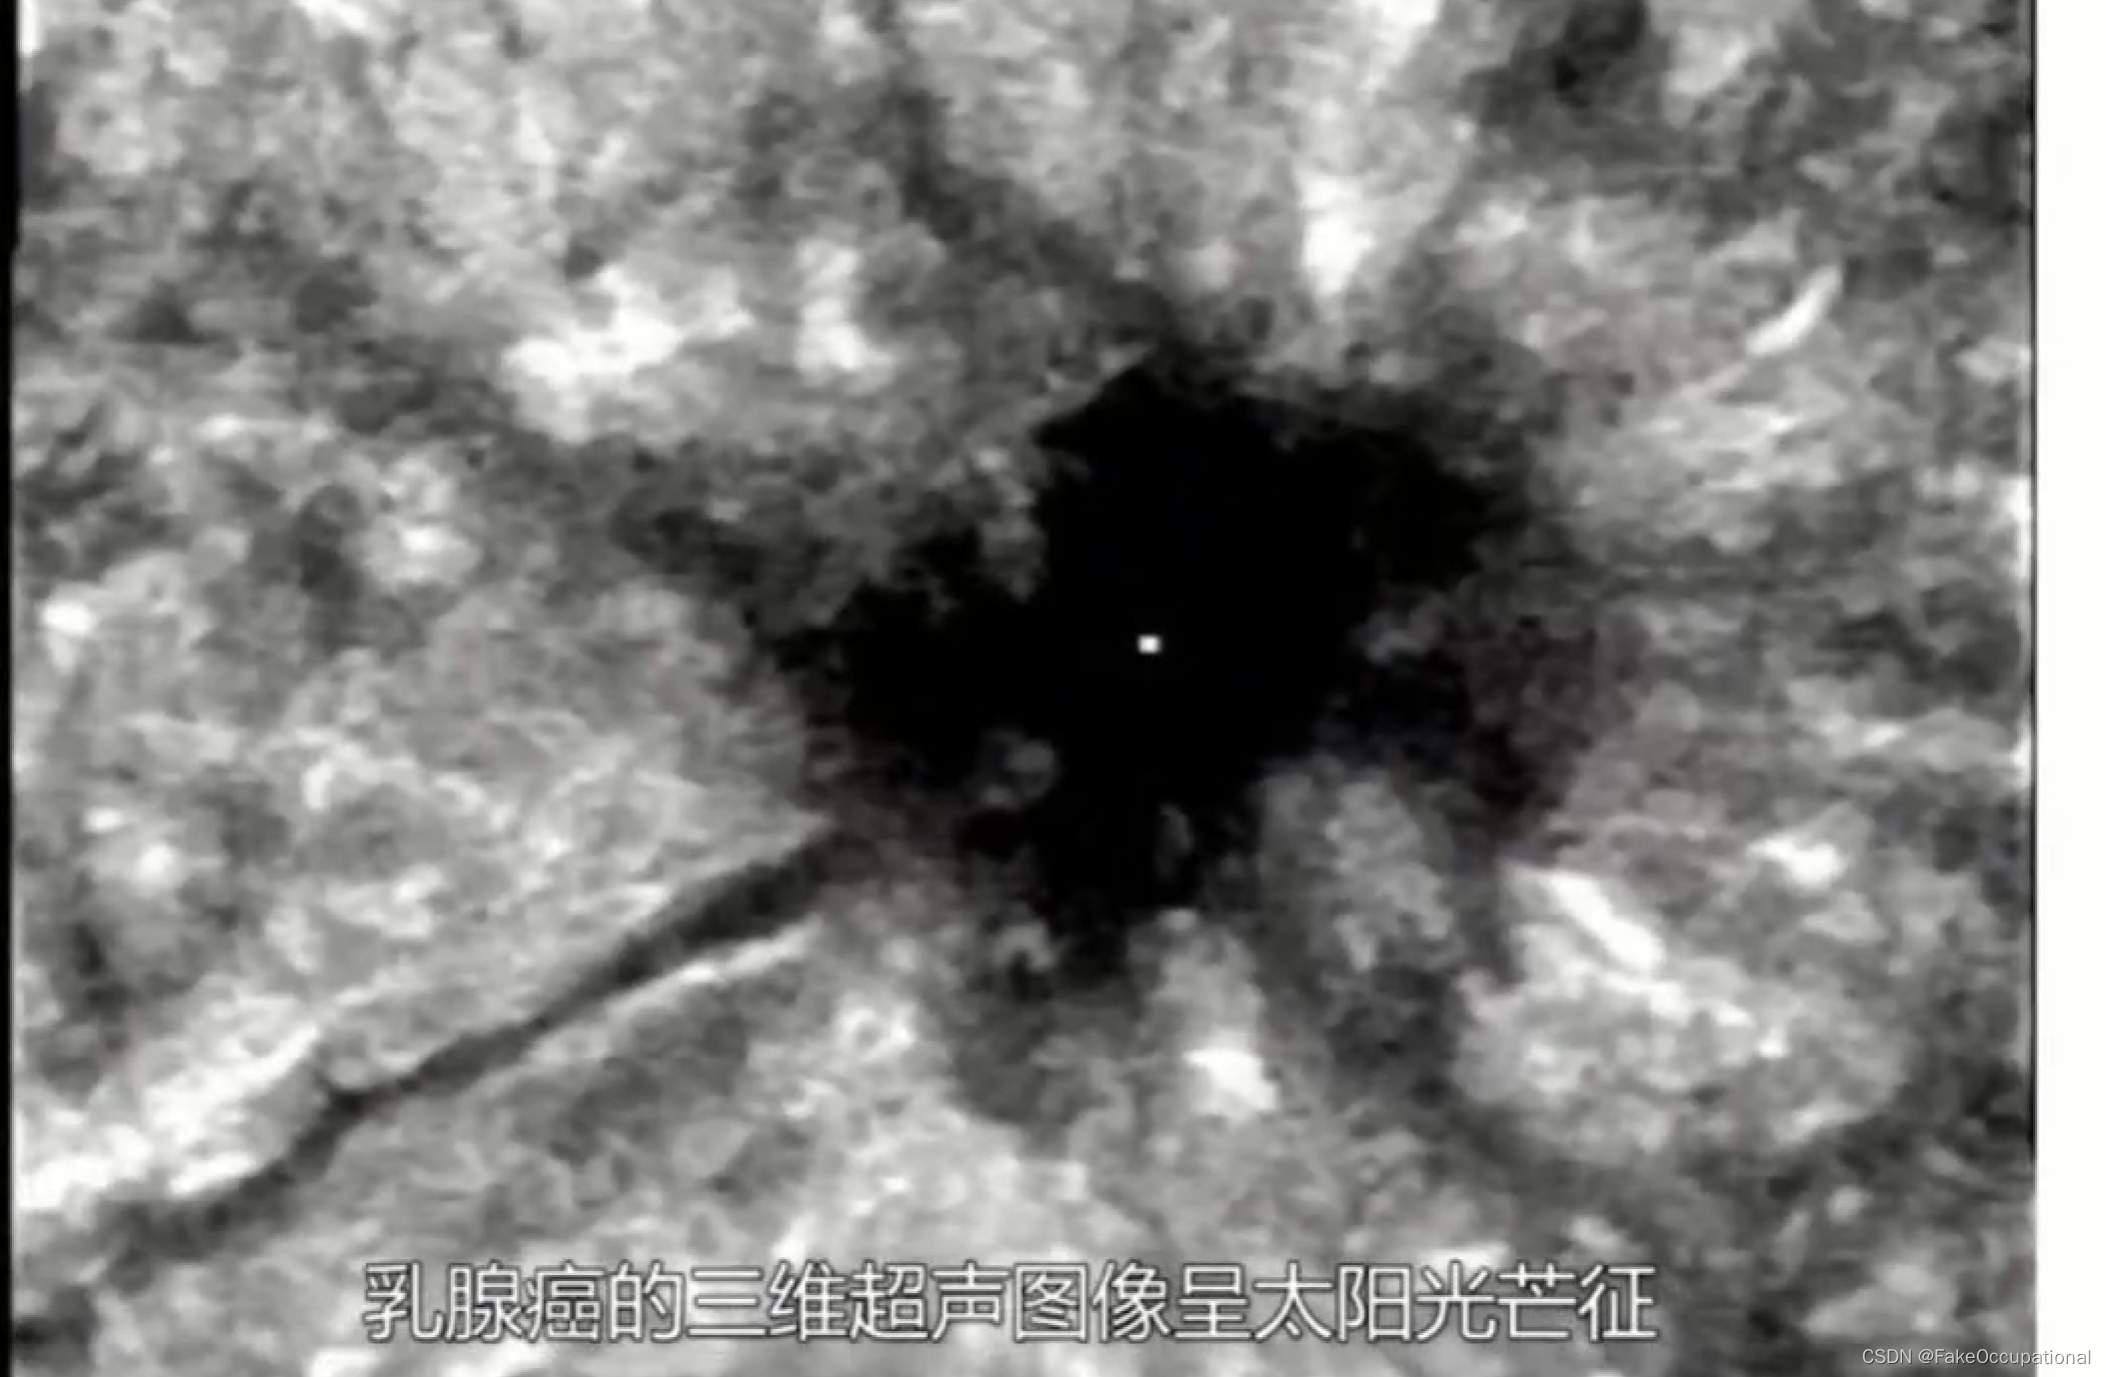

1.三维超声

乳腺癌

- 患者18岁,微小癌

- 其理论依据是恶性肿瘤常星离心性生长

- 淋巴结转移

乳腺超声进展